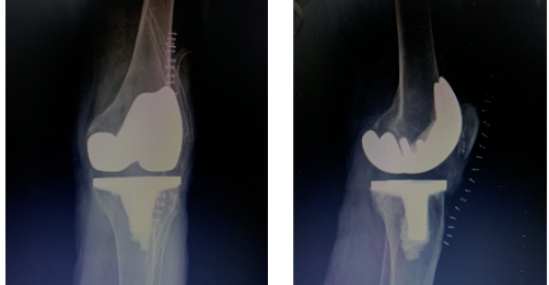

经过术前详尽的规划预演,王文波团队在术中导航系统的辅助下,仅花费一个小时便顺利完成手术。术后患者感觉疼痛明显减轻,第二天便下地行走。

王文波介绍,IKPAS全膝关节手术定位系统利用传感器技术,术中实时测量计算获得个性化的角度数据,不开髓就可帮助医生术中精准截骨,定位假体安装位置,手术伤口小,有效降低并发症的发生,患者术后体验好,缩短术后康复时间。